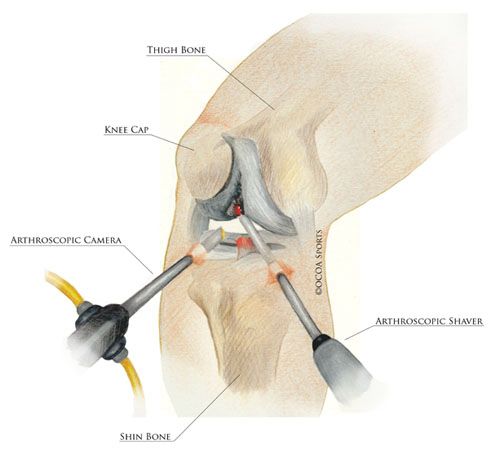

5. Advances in Arthroscopic ACL Surgery

Modern ACL reconstruction surgery is performed using minimally invasive arthroscopic techniques. These advances allow:

• Precise graft placement

• Minimal tissue damage

• Reduced post-operative pain

• Faster recovery

Surgical techniques can also be customized to suit the patient’s anatomy, sport, and activity level—leading to better functional outcomes.

ACL surgery involves three small arthroscopic incisions, usually about the size of a buttonhole.